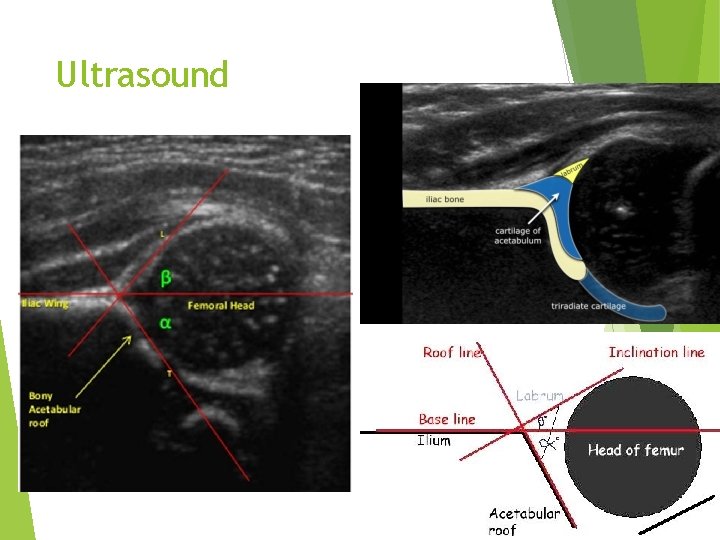

Ultrasound Base line : line pass through the ilium Alpa Angle : AA measures bony Acetabulum Normal more then 60 degrees Ø Beta Angle: BB la. Brum depth Normal less than 55 degrees BBB: Big Beta Bad

Ultrasound